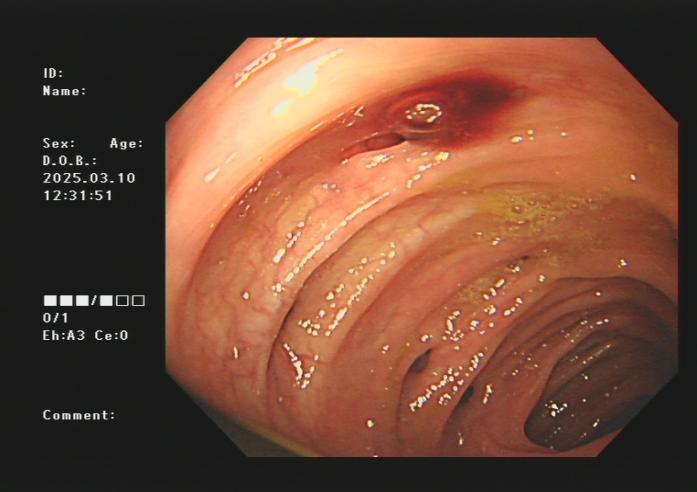

3.下消化道出血常见病因包括痔疮、肛裂、肠息肉、结肠癌、肠道憩室、炎症性病变(溃疡性结肠炎、缺血性肠炎、 感染性肠炎等)。以下是一些常见的下消化道出血内镜图片:

结肠憩室出血